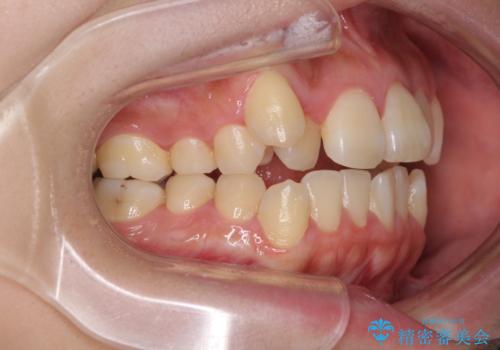

- 八重歯と叢生を気にして来院された患者様です。

上下の前歯が非接触であり、叢生や八重歯が顕著であったため、上顎左右第一小臼歯2本を抜歯して排列することとしました。

抜歯により移動量が多くなるため、ワイヤーや補助装置を活用し、その後インビザラインによる矯正治療を行うこととしました。

元々奥歯に負担のかかる咬み合わせですり減っていたため、仕上がった歯並びでも奥歯が咬んでいないように見えましたが、実際にはしっかりと咬合しており、患者様本人も咬んだ感触に違和感はないとのことでした。